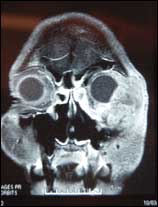

![]() |

| Figure 2. A preoperative x-ray scan shows the extent of the tumor. |